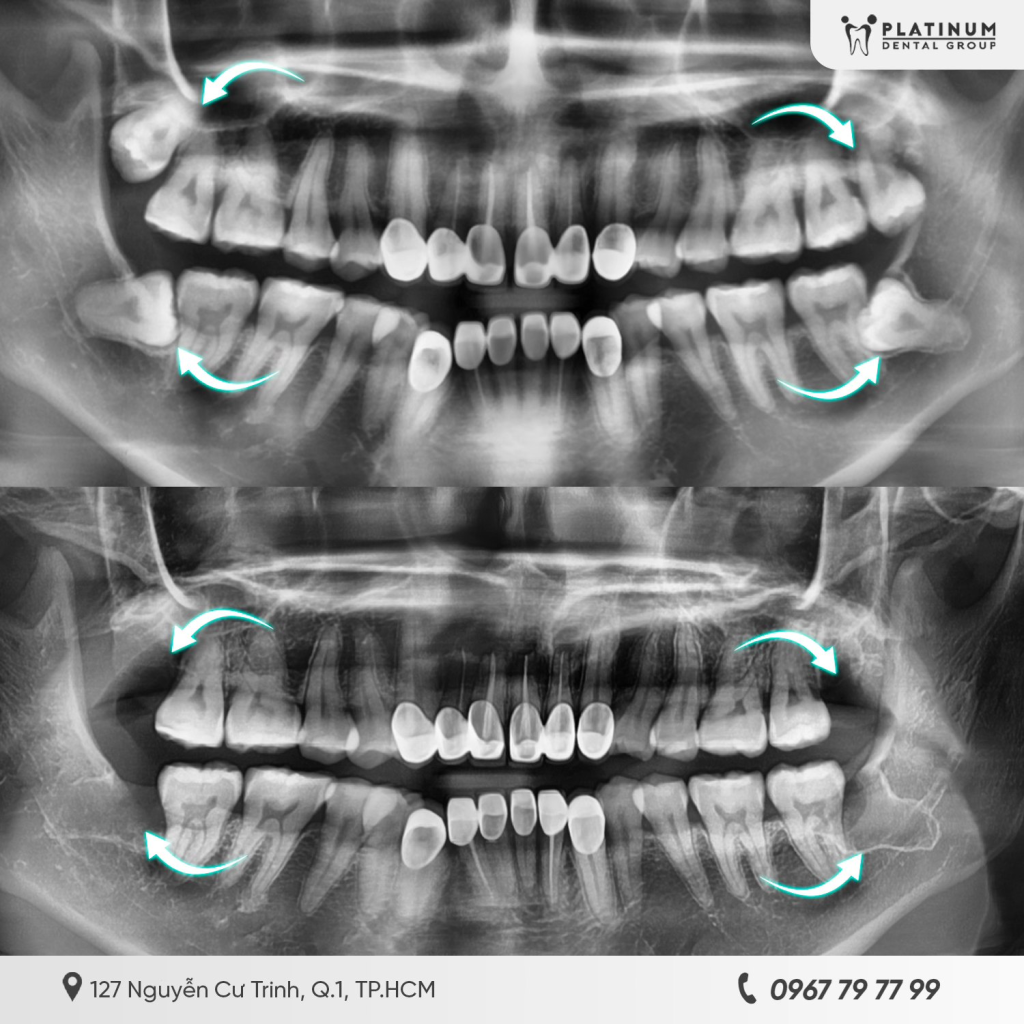

Chụp CT ConeBeam 3D xác định vị trí răng

Trước khi nhổ răng số 8, người bệnh thường được chỉ định chụp CT ConeBeam 3D. Hình ảnh 3 chiều cho phép bác sĩ quan sát rõ:

- Hướng mọc và mức độ mọc ngầm của răng

- Hình dạng và số lượng chân răng

- Khoảng cách giữa chân răng và dây thần kinh hàm dưới hoặc xoang hàm trên.

Nhờ đó, bác sĩ có thể tiên lượng mức độ khó của ca nhổ, lựa chọn kỹ thuật phù hợp và hạn chế tối đa nguy cơ tổn thương các cấu trúc giải phẫu quan trọng.

Răng số 8 mọc ngầm sâu, sát dây thần kinh hàm dưới

Răng số 8 mọc ngầm sâu, sát dây thần kinh hàm dưới là nhóm trường hợp cần đặc biệt thận trọng. Khi chân răng số 8 nằm gần hoặc chồng lên ống thần kinh hàm dưới, thao tác nhổ răng đòi hỏi kỹ thuật cao và sự hỗ trợ của hình ảnh CT 3D. Nếu không đánh giá chính xác, người bệnh có thể gặp tình trạng tê môi, tê cằm sau nhổ, đa phần là tạm thời nhưng vẫn gây lo lắng và ảnh hưởng sinh hoạt.

Răng số 8 mọc ngang, xoắn chân hoặc gần xoang hàm trên

Răng khôn mọc ngang hoặc có chân răng cong, xoắn làm tăng độ khó của ca nhổ. Đối với răng số 8 hàm trên, nếu răng nằm sát xoang hàm, nguy cơ thông xoang có thể xảy ra nếu thao tác không đúng kỹ thuật. Do đó, việc chụp phim và lựa chọn phương pháp nhổ phù hợp là yếu tố quyết định độ an toàn.